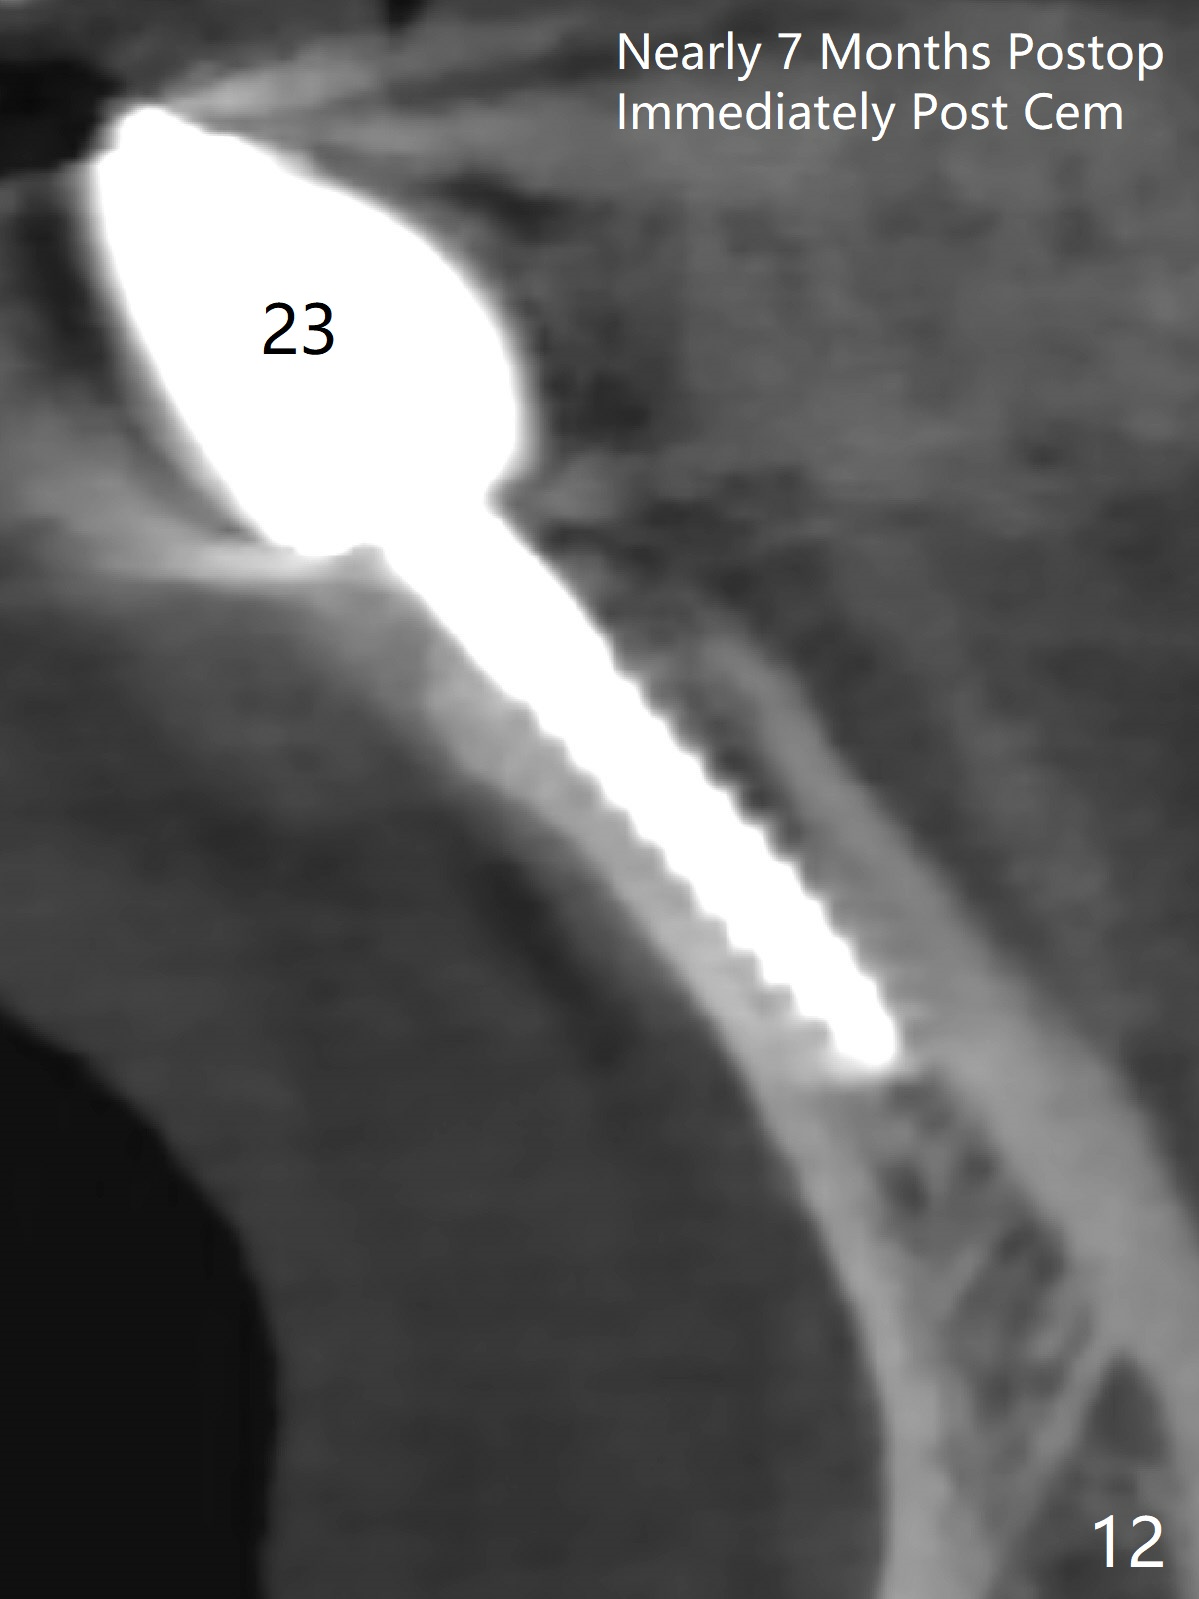

When the patient returns, the tooth #24 has exfoliated, while the ones at #25 and 26 has mobility III (Fig.1). The patient requests the tooth #23 extraction (Fig.2), but not #27. After SRP and extraction, osteotomy is initiated mesial to the sockets #23,25 and 26 (Fig.3,4) with intention to place 3 1-piece implants for 3 incisor crowns (Fig.5,6). Following Vanilla graft (Fig.5 *) a splinted provisional is fabricated to close the sockets (Fig.6). Peri-implant spaces close 5.5 months postop (Fig.7). Impression is taken after reprep for margin and parallelism (Fig.8). The final restoration consists of #23 single unit crown and #24-26 3-unit FPD (Fig.9). It appears that 2.5 mm 1-piece implants are not too small for the lower incisors (Fig.10-12), especially the central one (Fig.11). There may be perforation in the apical half of the lingual plate (L in Fig.10). The patient is not pleased with the shade of the #24-26 3-unit FPD (Fig.13 (6 months post cementation)). There is metal show through the abutments (*).